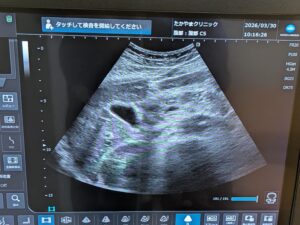

当院放射線科の特徴は、単純XP撮影での撮影・骨密度検査・超音波検査(エコー)などの画像診断を担当しています。撮影・検査後の画像や読影診断レポートを電子カルテと共有し、迅速な治療方針の決定に大きく貢献しています。骨密度検査は精度の高い骨密度測定器を導入しています。また、超音波検査(エコー)は、頸動脈(動脈硬化)・甲状腺・腹部等の検査を行っています。検査をご希望の方は、お電話でご連絡いただくか、お気軽にスタッフにお尋ねください。